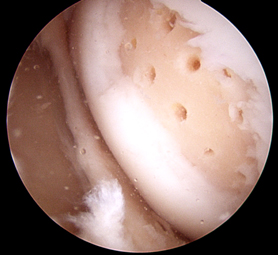

Step 4:

Bleeding occurs from holes